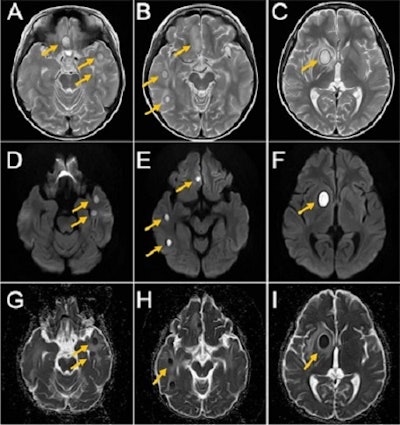

Magnetic resonance imaging (MRI) revealed exacerbation of his brain abscess and circumferential swelling. The patient was transferred to another hospital, and placed on the same course of antibiotic treatment, the authors wrote.

At the new hospital, the boy underwent a whole-body MRI to identify the fungus and source of infection. The MRI revealed several lesions in his frontal lobe, basal ganglia, thalamus, and bilateral temporal lobes. Due to these findings, clinicians suspected a blood-based infection due to multiple brain abscesses, they wrote.

One month after his teeth were pulled, the boy underwent an MRI that revealed that the brain abscess was still there but noticeably reduced. On November 17, he was discharged from the hospital.